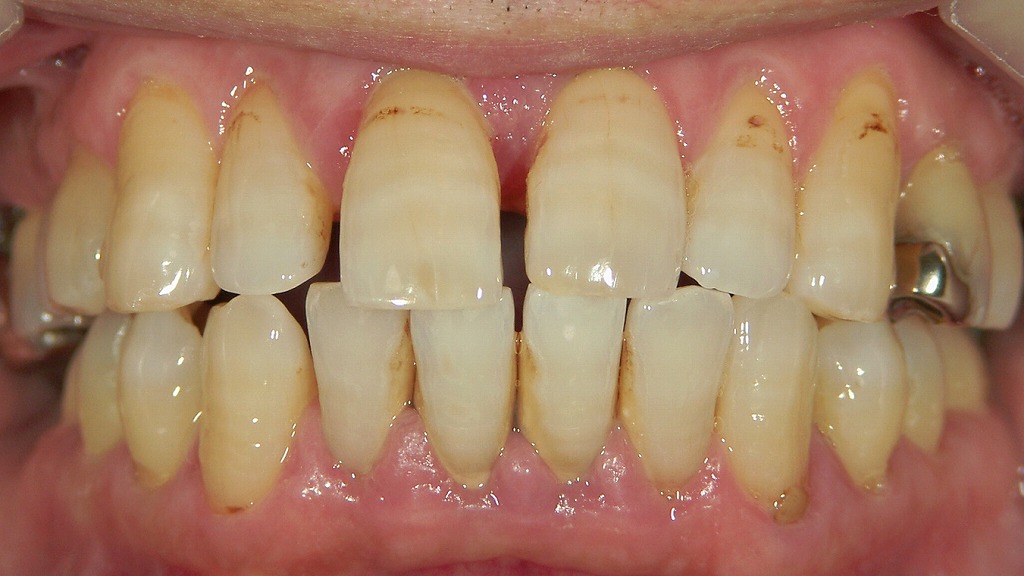

画像でも見られるように、

前歯部に多数の隙間が見えるのは 歯周病による典型的変化 です。

歯周病の進行によって起こるフレアアウト(前歯の倒れ込み)症例

下顎前歯の舌側に大量の歯石が付着し、歯周病が進行している状態です。

歯を支える骨や歯周組織が弱くなると、前歯は内側からの舌の圧や噛み合わせの力に耐えられず、徐々に前方へ倒れ込む「フレアアウト」を起こします。